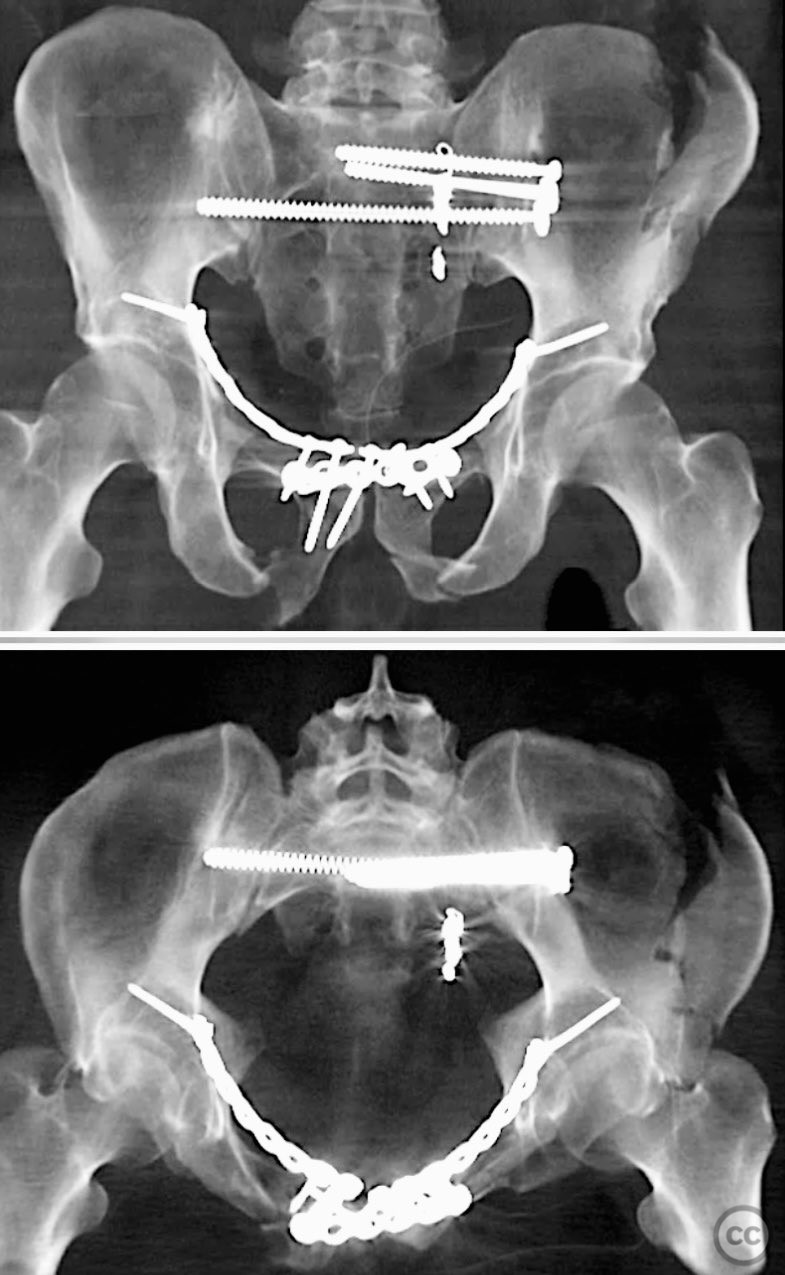

Clinical and radiological findings:  A 42-year-old male sustained a high-energy motor vehicle accident resulting in an unstable pelvic ring injury (AO/OTA 61-C1.3) with hemodynamic instability and associated intraperitoneal bladder rupture. Initial computed tomography demonstrated a complex anterior pelvic ring disruption and a posterior sacral fracture with contrast extravasation and blood within the fracture site. The patient was hemodynamically unstable on presentation.

Planning remarks:  The preoperative plan included multidisciplinary management with urology for bladder repair, followed by open reduction and internal fixation of the anterior pelvic ring via an anterior approach. Subsequent posterior pelvic stabilization was planned after initial resuscitation and anterior fixation, utilizing a posterior approach for direct sacral reduction and percutaneous iliosacral screw fixation.

Anatomical surgical approach:  The anterior approach utilized a Pfannenstiel incision to access the symphysis pubis and pubic rami, with subperiosteal dissection of the rectus abdominis and exposure of the retropubic space for reduction and fixation. For posterior sacral ORIF, a midline longitudinal incision was made over the sacrum, with subperiosteal elevation of the paraspinal musculature to expose the sacral fracture. A tenaculum clamp was applied for direct reduction, followed by percutaneous insertion of iliosacral screws under fluoroscopic guidance.

The case was notable for initial successful multidisciplinary management of both hemodynamic instability and intraperitoneal bladder injury, allowing for staged surgical intervention. Despite accurate anterior pelvic reduction and fixation, postoperative imaging revealed worsening posterior sacral displacement, necessitating subsequent posterior open reduction. The use of a tenaculum clamp facilitated direct anatomical reduction of the sacral fracture prior to iliosacral screw fixation. The presence of an embolic coil from prior angioembolization did not impede surgical access or hardware placement. This case demonstrates that initial anterior pelvic ORIF does not complicate or preclude subsequent routine posterior pelvic ORIF in complex unstable ring injuries.

Orthopaedic implants used:   Anterior pelvic reconstruction plate, iliosacral cannulated screws, tenaculum reduction clamp